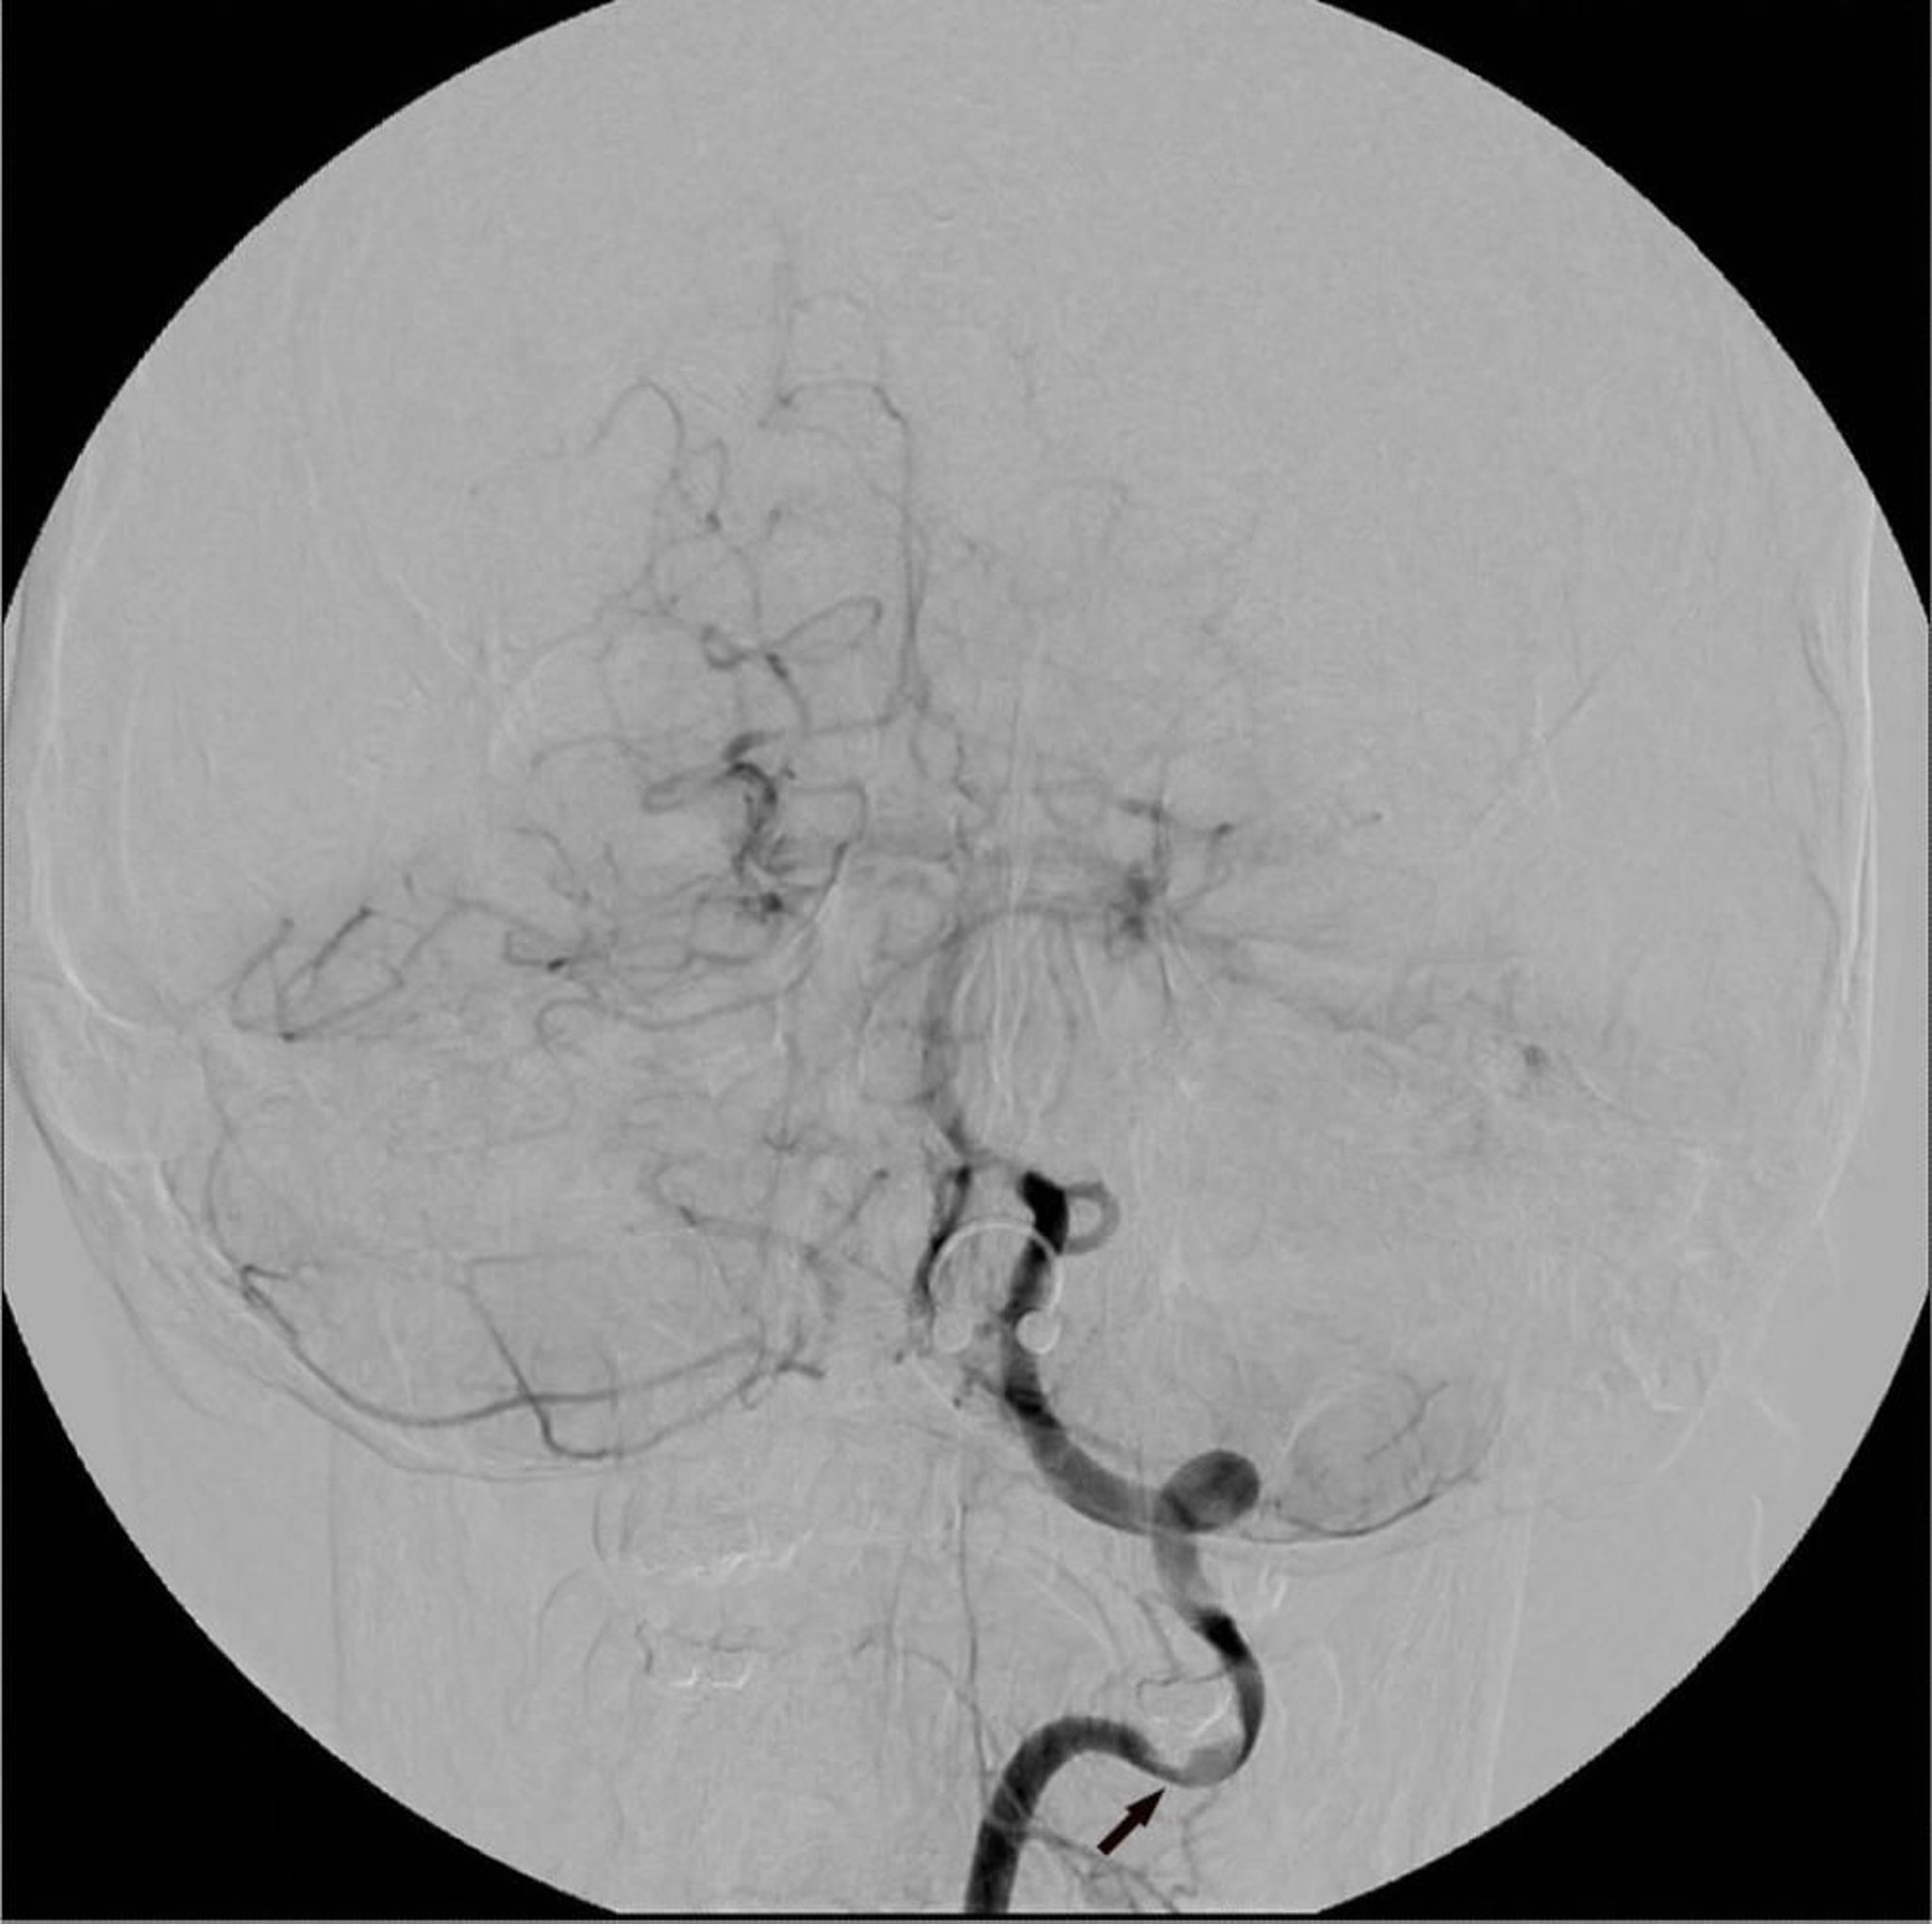

Chụp mạch số hóa xóa nền (DSA) động mạch đốt sống trái cho thấy một vùng hẹp khu trú (mũi tên).

Hình ảnh do bác sĩ Hakan Ilaslan cung cấp.